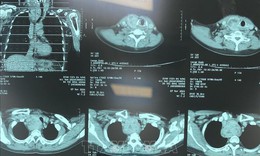

Hàng trăm nhà khoa học quốc tế và Việt Nam 'hội tụ' bàn giải pháp nâng chất lượng chẩn đoán, điều trị ung thư phổi

Y tế - 10/10/2025 08:50SKĐS - Thứ trưởng Trần Văn Thuấn cho rằng, hội nghị Ung thư phổi Châu Á 2025 được tổ chức tại Việt Nam không chỉ là một sự kiện khoa học, mà còn là minh chứng cho niềm tin và sự công nhận của cộng đồng quốc tế đối với năng lực và cam kết của Việt Nam trong lĩnh vực y học và chăm sóc sức khỏe toàn dân.